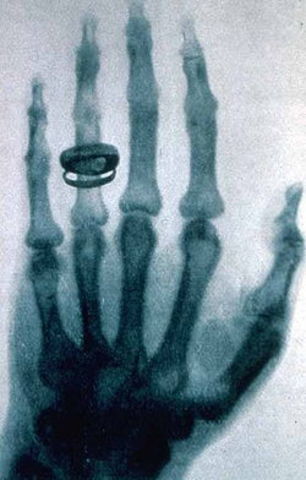

• Descubrimiento de los Rayos X

Descubrimiento de los Rayos X

Uno de los avances relevantes en la historia de la humanidad ha sido el descubrimiento de los rayos X, Esto fue posible gracias al estudio, observación y experimentación del físico alemán Wilhelm Röentgen, quien "al observar que las placas fotográficas resultaban sensibilizadas cuando en su proximidad existían cargas eléctricas producidas por válvulas de alto vacío" (Yankovic, 2010)

Wilhelm fue galardonado con un Premio Novel en Física en el año 1901debido a su gran descubrimiento.